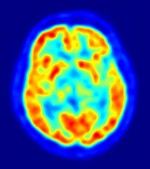

Did you know that only 3% of your brain’s processing power, is used by your conscious mind and the other 97% is subconscious, unconscious, autonomic, automatic. Isn't that amazing! For instance, you don’t have to think about how to breath, blink your eyes or move your arm right? All these things happen on automatic pilot. Scientists have found that the power of your unconscious mind is perhaps a million times greater than that of your conscious mind. So imagine how powerful you would be if you get their unconscious mind onboard with your intention and will. We normally try to make [...]